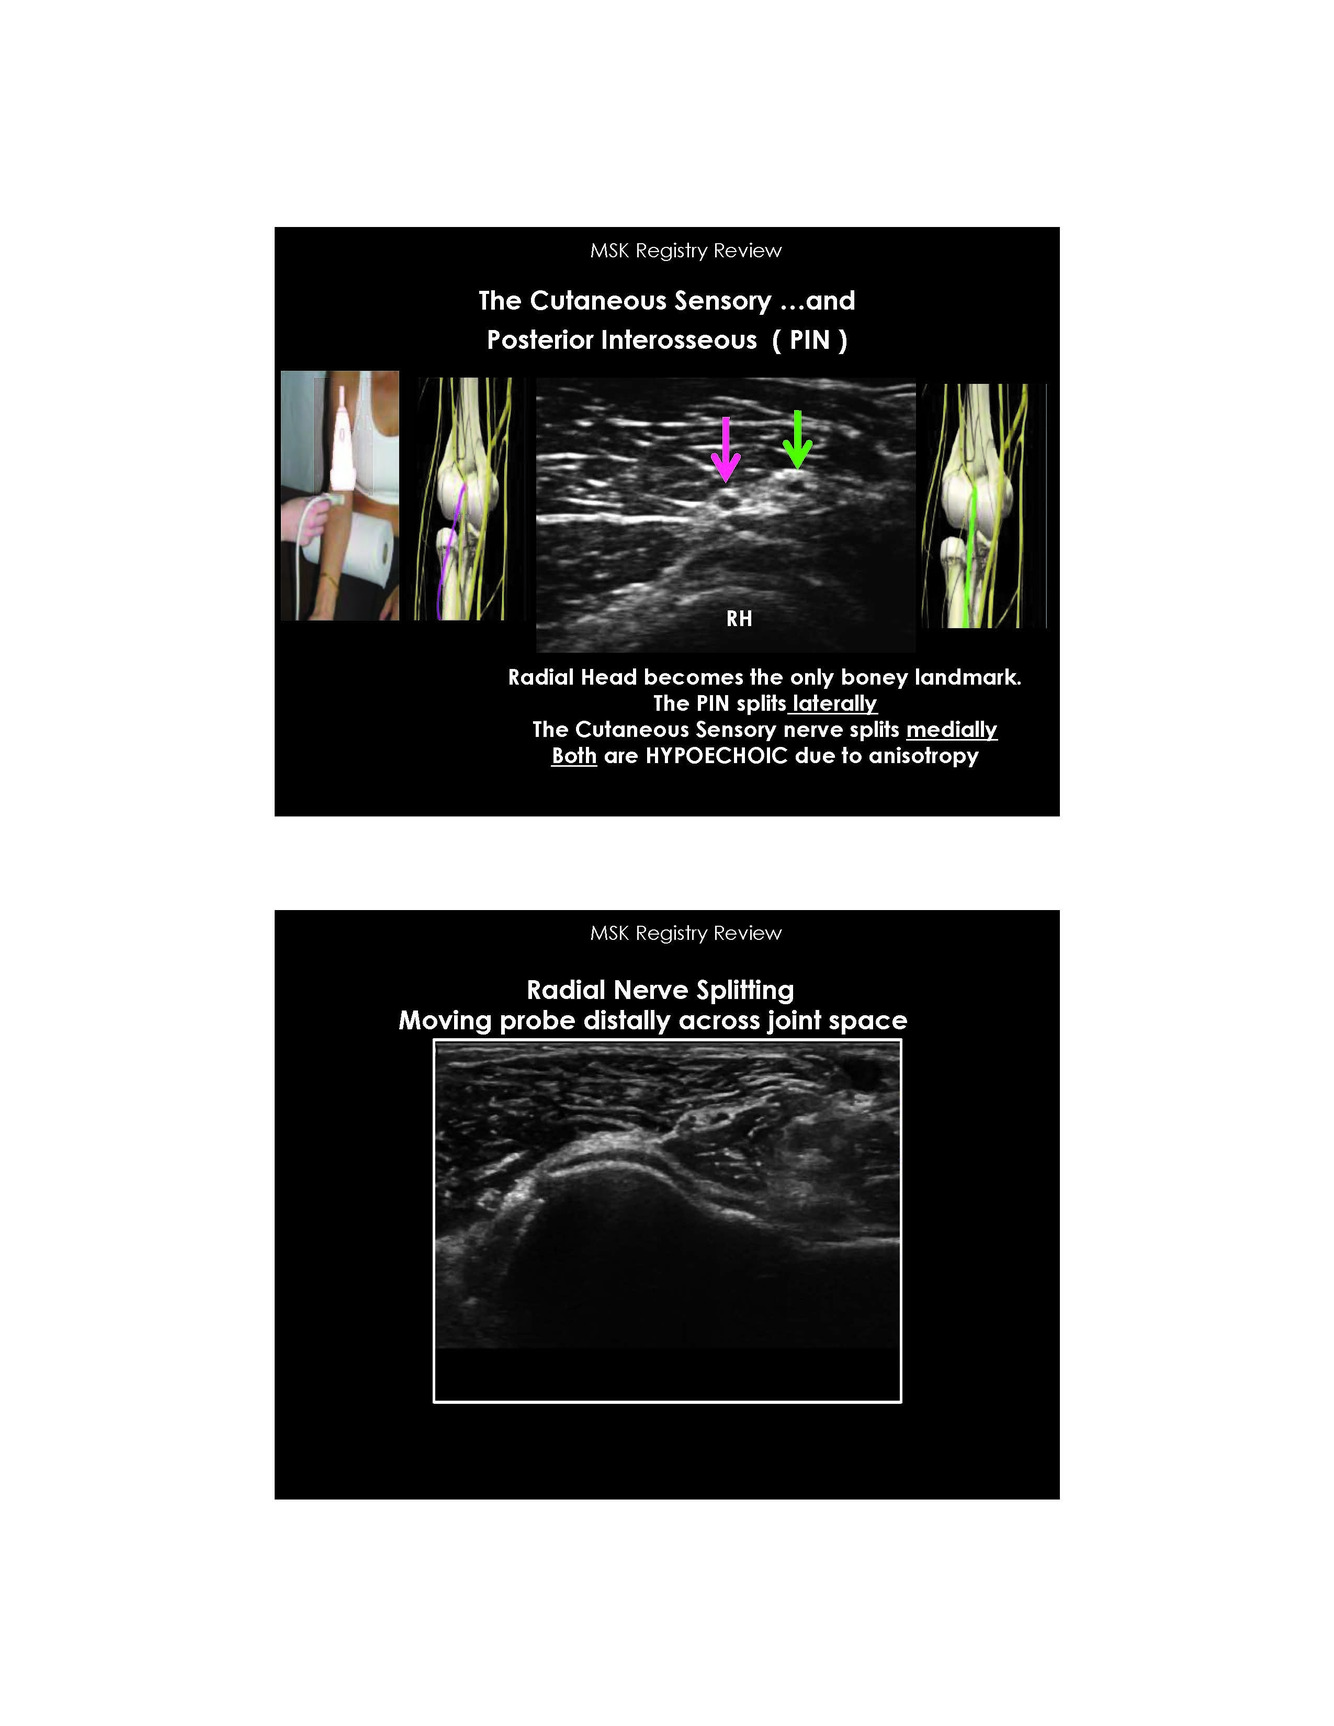

Location of split from the radial nerve where does the cutaneous sensor and posterior interosseous go

The PIN splits laterally and cutaneous sensor splits medially

Image of the PIN

Note bony landmark